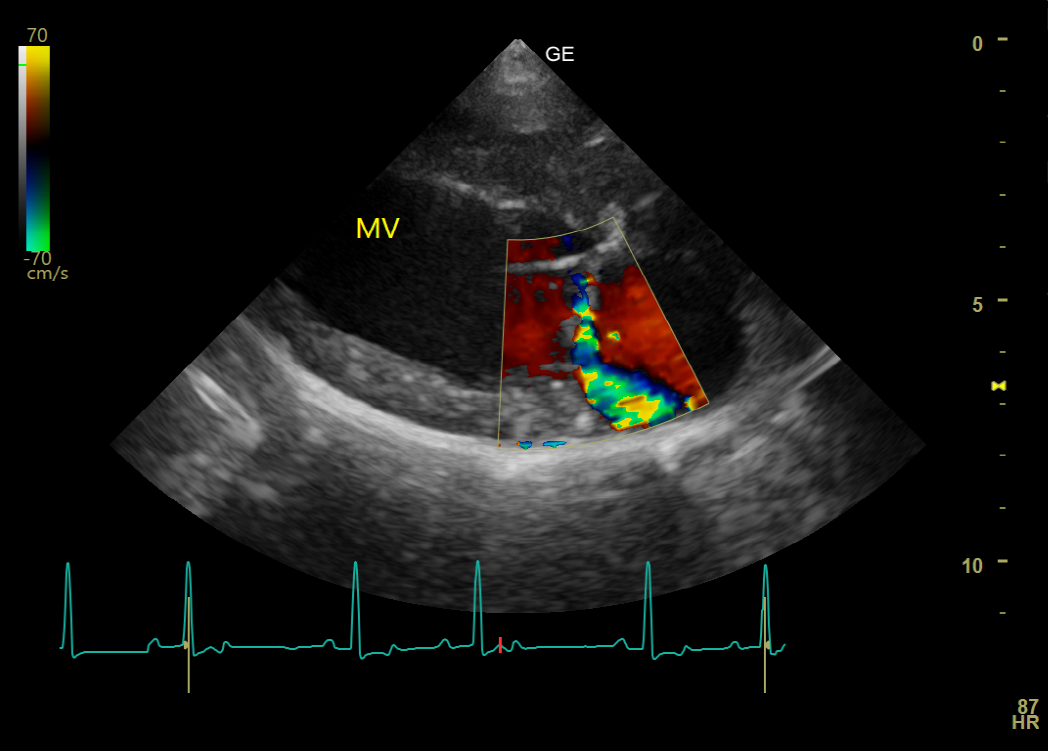

Leidet Ihr Tier an einer Herzerkrankung, kann diese mittels Auskultation (Abhören des Herzens) erkannt werden. Sind während der Auskultation des Herzens pathologische Geräusche des Herzens hörbar, empfiehlt sich eine Herzultraschalluntersuchung, die im Kleintierzentrum Landwasser routinemäßig durchgeführt wird. Dies ermöglicht eine genaue Diagnose des Herzleidens. Eine Sedierung des Tieres ist nicht notwendig und Sie können bei der Untersuchung selbstverständlich dabei sein. Wir haben mehrere Ultraschallköpfe zur Verfügung, um die kardiologische Untersuchung angepasst an die Größe Ihres Tiers durchzuführen. Mittels Farbdoppler können Blutströmungen in allen vier Herzkammern farblich dargestellt werden. Treten Undichtigkeiten der Herzklappen, pathologische Turbulenzen, Form- oder Größenveränderungen der Herzwand oder angeborene Herzdefekte auf, werden diese im Herzultraschall diagnostiziert und in ihrer Schwere klassifiziert, damit eine optimale Therapie gefunden werden kann.